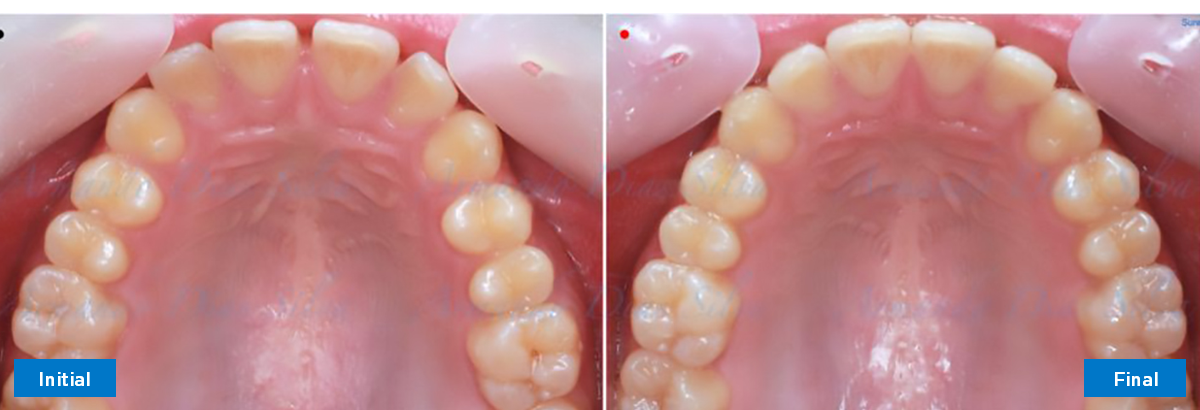

Clase II, Div. 1: Protrusión del incisivo central y espacios anteriores (SureSmile® Aligners)

Principal queja del paciente: Protrusión del incisivo central y mordida abierta. El paciente rechaza la expansión del arco palatino (MARPE) y las extracciones.

Este paciente adolescente presenta molares de Clase II y no le gusta su mordida abierta ni lo protrusivos que son sus dientes frontales. Por sus fotografías faciales, parece que su mandíbula es retrognática o le falta volumen en la barbilla. El historial del paciente también indica que existe un problema funcional al no haber guía de los incisivos.

Diagnóstico

• Molares de clase II

• Diastema

• Espaciamiento leve de las arcadas superior e inferior (deficiencia transversal de 3,45 mm)

• El primer molar superior derecho está en una posición más mesial que el primer molar superior izquierdo

• Deficiencia transversal maxilar leve (3,45 mm)

• Incisivos superiores e inferiores proclinados

• Orientación canina desfavorable

Se logran todos los objetivos principales:

• Molares de clase I logrados con distalización y sin elásticos

• Sin cambios en la posición del cóndilo

• Sin expansión maxilar, respetando la envoltura periodontal

• Incisivos inferiores retroinclinados, que mejoran la estabilidad a largo plazo